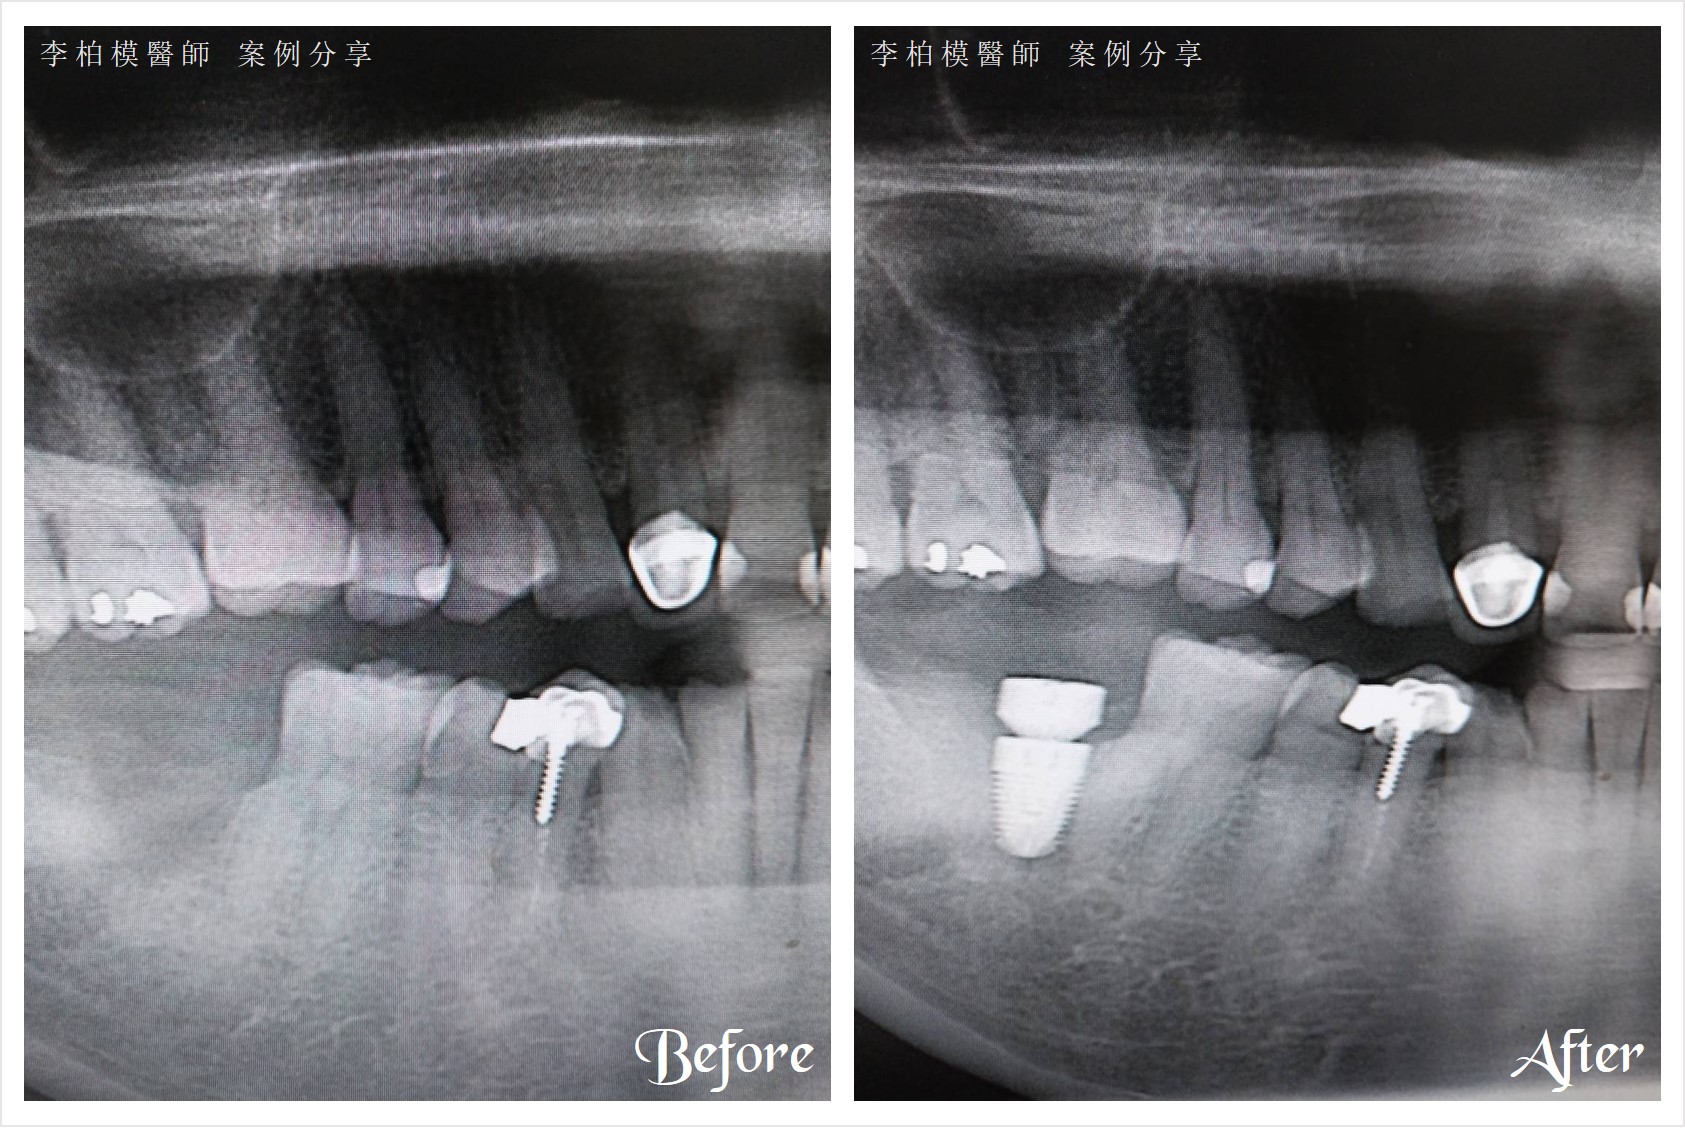

▲#1

李醫師幫患者處理,一顆植了12年的植體掉落,留下一個火山口般的缺口。

李醫師迅速處理,在清理後立即重新植入新植體,和補骨一次完成。

3天後電話慰問,患者說一切正常,恢復順利。